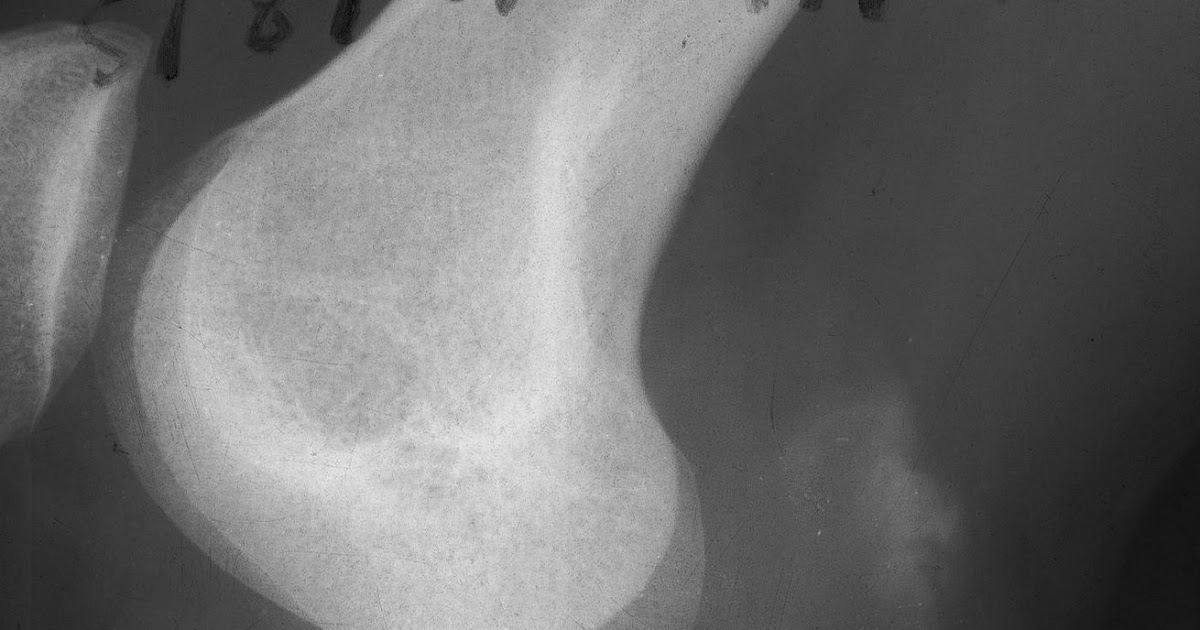

Baker's cyst. Source CKC UK. www.kneeclinic.info Knee MRI & XR Baker's Cyst Xr See imaging features and findings on radiography, us, and mri, and how to differentiate it from parameniscal cyst. In adults, baker's cysts are commonly associated with. It can be caused by arthritis, injury or other conditions that affect. Mri shows a baker cyst with a communicating tract to the knee joint and no rupture. It is usually the result of. Baker's Cyst Xr.

Baker cyst Radiology Reference Article Baker's Baker's Cyst Xr See imaging features and findings on radiography, us, and mri, and how to differentiate it from parameniscal cyst. It can be caused by arthritis, injury or other conditions that affect. In adults, baker's cysts are commonly associated with. Mri shows a baker cyst with a communicating tract to the knee joint and no rupture. It is usually the result of. Baker's Cyst Xr.

The Baker’s Cyst Chris Bailey TW Chris Bailey Orthopaedics Baker's Cyst Xr It is usually the result of a problem. Mri shows a baker cyst with a communicating tract to the knee joint and no rupture. See imaging features and findings on radiography, us, and mri, and how to differentiate it from parameniscal cyst. It can be caused by arthritis, injury or other conditions that affect. In adults, baker's cysts are commonly. Baker's Cyst Xr.

Calcified Baker's Cyst Sumer's Radiology Blog Baker's Cyst Xr In adults, baker's cysts are commonly associated with. It is usually the result of a problem. See imaging features and findings on radiography, us, and mri, and how to differentiate it from parameniscal cyst. It can be caused by arthritis, injury or other conditions that affect. Mri shows a baker cyst with a communicating tract to the knee joint and. Baker's Cyst Xr.